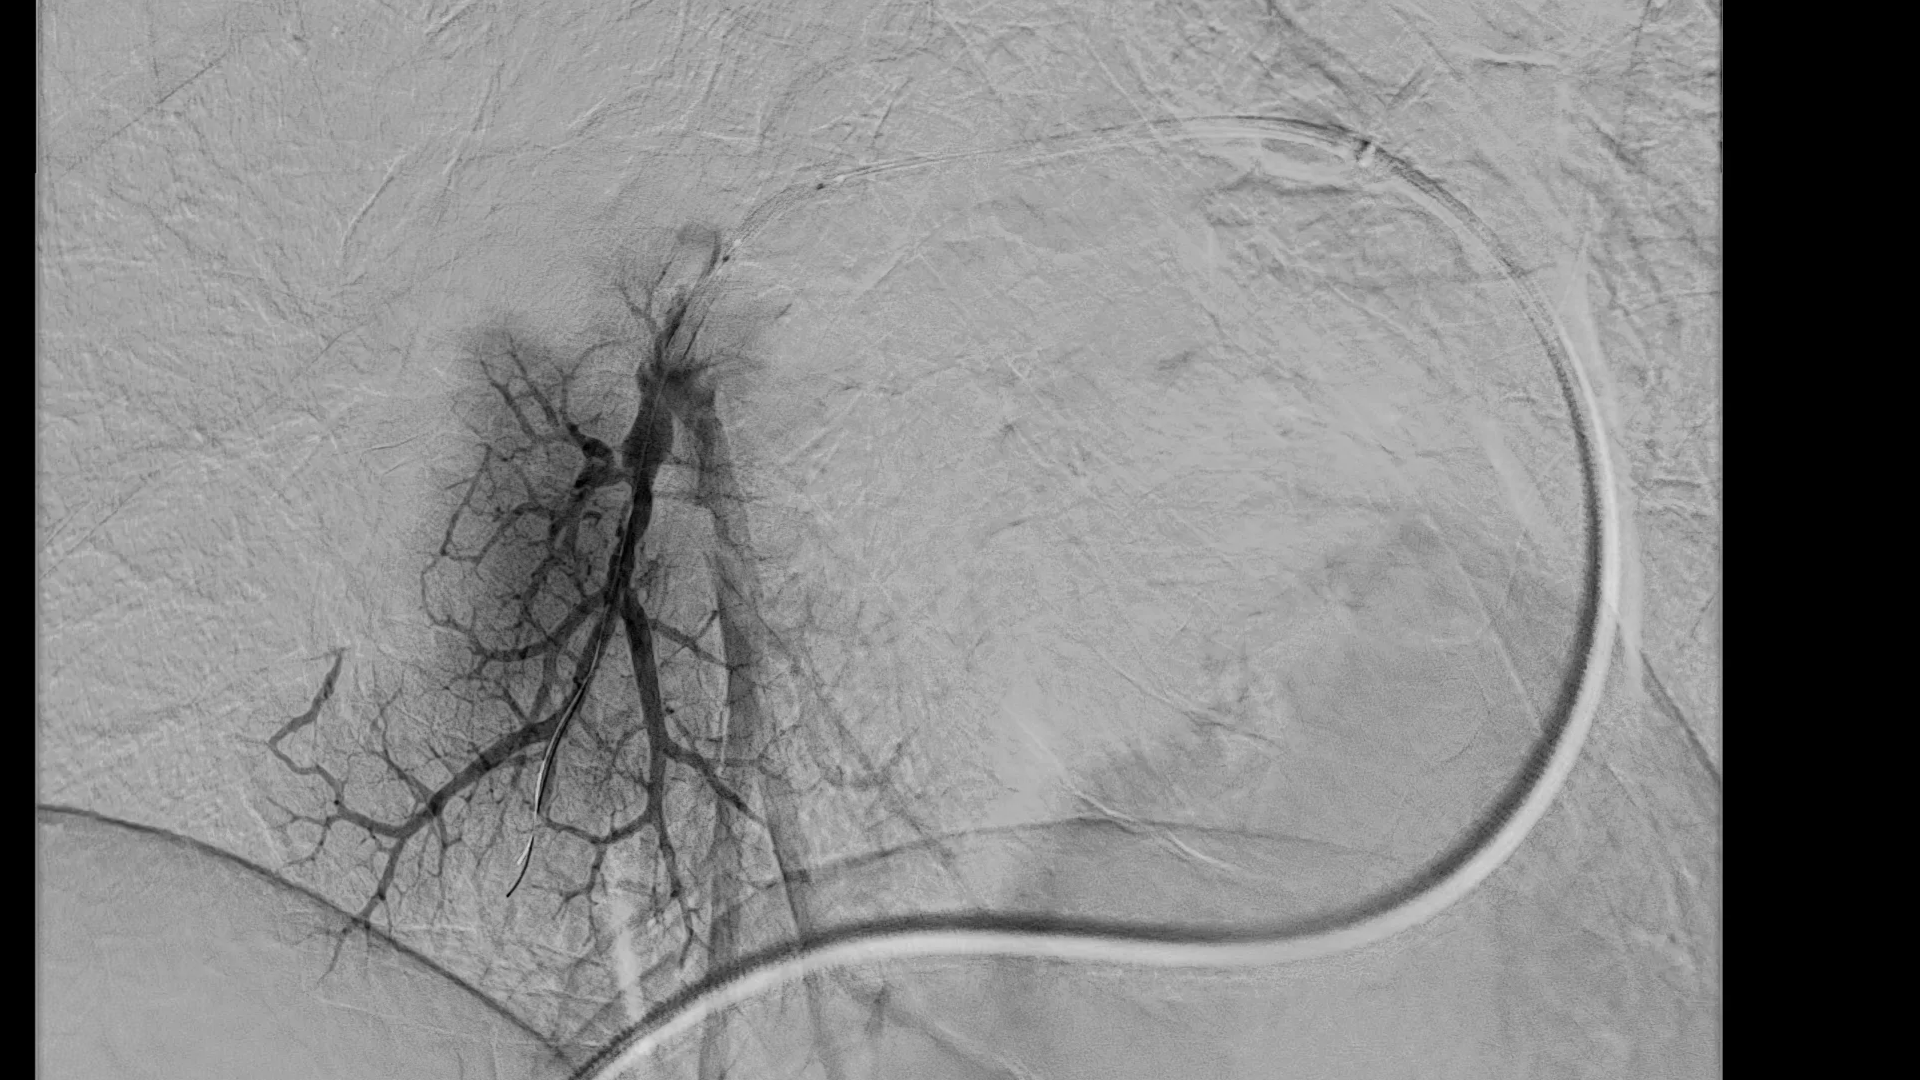

Azurion 7 B20/15 разработана для стабильного качества изображения при минимизации радиационной нагрузки на пациента и персонал. Бипланарная геометрия (20″ фронт + 15″ латераль) обеспечивает крупное поле обзора и проекционную гибкость в сложных доступах: нейроинтервенции, вмешательства на сонных артериях, ШВА, коронарные и периферические процедуры. Инструменты визуализации и навигации, включая Dynamic Coronary Roadmap (динамическая «дорожная карта») и StentBoost Live (усиление видимости стентов), повышают точность позиционирования проводников и устройств, сокращая количество контрольных инъекций контраста.

| Режимы | Флюороскопия, кинорежим, DSA; ротационная 3D-ангиография (SmartCT) |

| Назначение | Нейроинтервенции, коронарные и периферические вмешательства |

- Нейроваскулярные вмешательства: диагностика и лечение внутричерепных/сонных сосудов.

- Интервенционная кардиология: коронарография, PCI, визуализация и позиционирование устройств.

- Периферическая ангиография и эндоваскулярные процедуры.